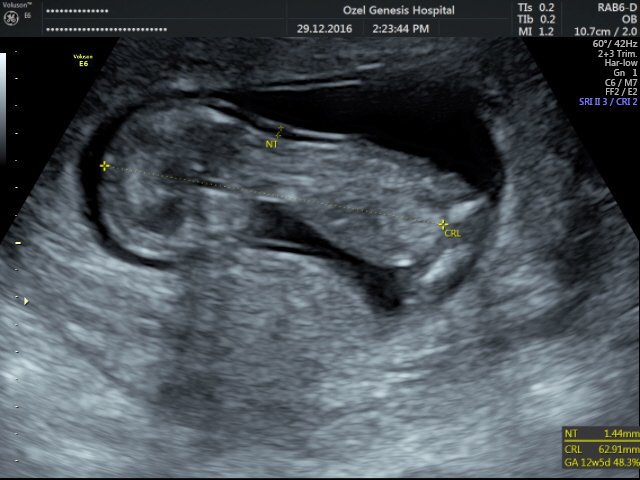

E Efsa35 Yeni Üye Üye 20 Ocak 2017 #144 Merhaba benim bebiş 12 haftalık cinsiyeti ne olabilir şimdiden teşekkür ederim

Sevimli cadı Daimi Üye Üye 20 Ocak 2017 #145 merhaba görsel net olmadığı için değerlendirme yapamıycam. Allah hayırlı doğumlar nasip etsin